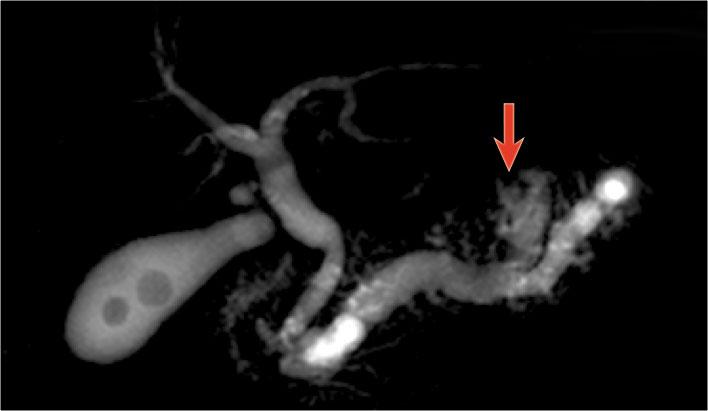

MRCP cho thấy cả IPMN thể ống chính lẫn thể ống nhánh (mũi tên).

IPMN là tổn thương có tiềm năng ác tính.

Các dấu hiệu ác tính bao gồm:

- Ống tụy > 8 mm – như trong trường hợp này.

- Nốt đặc trong lòng ống.

- Khối xung quanh ống tụy.

- Giãn ống mật chủ.